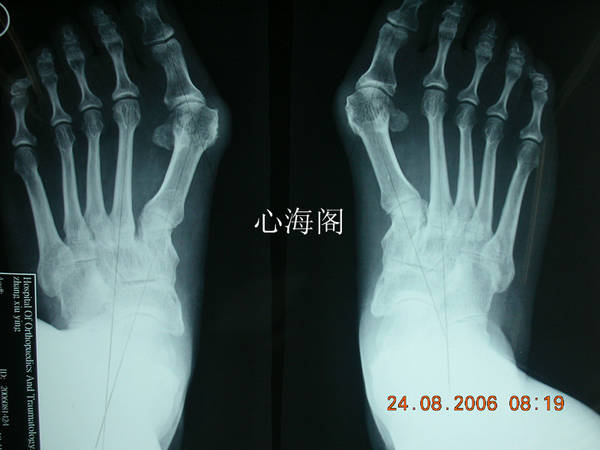

患者,女,56岁,双足拇外翻行微创截骨矫形术。

放松一下,几年前的作品,微创做的,不缝针。不打石膏。

最后两张图片是一个人吗?

术前和术后吗?

拍照时间编辑了吗

最后两张图如果拍照时间无误的话,那很明显不是同一个人啊~~楼主,做人要厚道~~

对不起。没编辑,搞错了。但手术效果非常好。谢谢大家关注。拍砖。我以后会注意发帖照片。我是和北京望京医院温建民教授学的。

17楼主,我要不厚道,编辑个时间应该不难,我只是想让大家看一种拇外翻微创截骨矫形术。